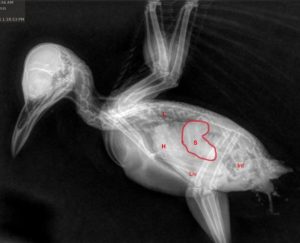

Rehab Fact: Avian Malaria

When you think of malaria, you probably think of the tropics – after all, that’s where humans can be infected. For birds though, malaria is worldwide, present on every continent except Antarctica (at least for now). Birds across the world have evolved with dozens of malaria species, and most of the time are only subtly affected. However, changing infection and environmental dynamics have altered this balance, sometimes in dramatic ways. Invasive malaria has caused the extinction of about a third of Hawaii’s honeycreeper species since the late 1800’s, and other introduced strains, global warming and environmental toxins have made malaria infections more dangerous over time. But before we get into how it affects Vermont’s birds, what exactly is malaria?

Malaria is caused by a single celled parasite in the genus Plasmodium, that has a complex life cycle involving both mosquitoes and vertebrate hosts. Briefly, an infected mosquito bites a bird, human, or other animal, and the parasites are transmitted in the saliva. They initially undergo asexual reproduction in tissue cells, then invade red blood cells. Once the blood is infected, gametes, the mature parasites, can be taken up by a mosquito to continue the infection cycle. A second form, called schizonts, develop into clusters of smaller forms called sporozoites, and when the schizont is mature it ruptures the red blood cell, allowing the sporozoites to spread and infect other red blood cells. Destruction of red blood cells leads to anemia, which can cause weakness, circulatory disorders and kidney damage. The red blood cell turnover also leads to a greatly enlarged liver and spleen, which can put pressure on the air sacs and contribute to respiratory difficulty. Somewhat unique to birds, tissue stages can also cause severe disease or death, particularly when the cells that line blood vessels become infected and swollen, which can lead to blockages that prevent blood flow to parts of the brain. Finally, immune compromise from malaria infection can lead to high rates (>40%) of severe bacterial and fungal coinfections, making treatment substantially more difficult.

So what birds in Vermont are affected by malaria? It was first discovered in Northeastern common loons in 2017, and has caused mortalities each year, making it an emerging disease, although luckily it hasn’t seemed to cause major impacts so far. The more widespread effect is in passerines, which is where nearly all cases have been seen in CWBR. It is primarily a disease of juvenile birds, particularly American robins, corvids and grackles. In fact, in some years it is a leading cause of infectious disease deaths in robins, with 7 cases and 5 deaths in 2025- making it responsible for 25% of deaths in care for robins this year. I suspect that it is an underrecognized disease in juvenile passerines, for a variety of reasons: many rehabilitators either don’t or can’t do bloodwork on songbirds, or don’t perform necropsies regularly. Additionally, many field studies on malaria focus on breeding or migrating adults, and don’t focus on the population most vulnerable to infectious diseases- young birds. This has been an area of ongoing research for me, to better understand pathology in wild birds, improve ability to detect and identify coinfections, use these findings to guide treatments and ultimately to publish these findings and increase awareness about this significant disease of wild and rehabilitated birds.